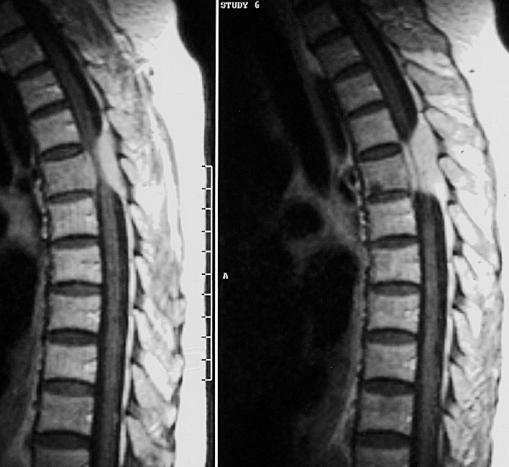

脊柱骨折:纵轴性暴力冲击,脊柱骤然过度前屈。X线表现为椎体压缩楔形变,前缘骨皮质嵌压,见横行不规则致密带,有时前方有分离的碎骨片,椎间隙正常,可合并脊椎后突成角;CT可充分显示脊椎骨折类型,骨碎片移位情况,椎管内骨碎片及狭窄情况。

X线平片:椎体压缩性骨折,可合并附件骨折

CT:观察骨折对脊髓和神经根的影响。 MRI:观察椎体骨折形态及信号(新鲜期T1低、T2高)、椎间盘 损伤、脊髓挫裂伤和受压、韧带撕裂

椎体爆裂骨折;单纯压缩骨折